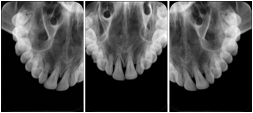

2. A patient requests cosmetic surgery to enhance their facial appearance. The case requires consultation between an orthodontist in New York and an oral surgeon in California. The cephalometric series of 2D projections constructed from a volumetric CT data set that is used for the discussion is arranged by a Structured Display for transfer between the two practitioners.

Cephalometric Series Structured Display

Figure OO-2. Cephalometric Series Structured Display